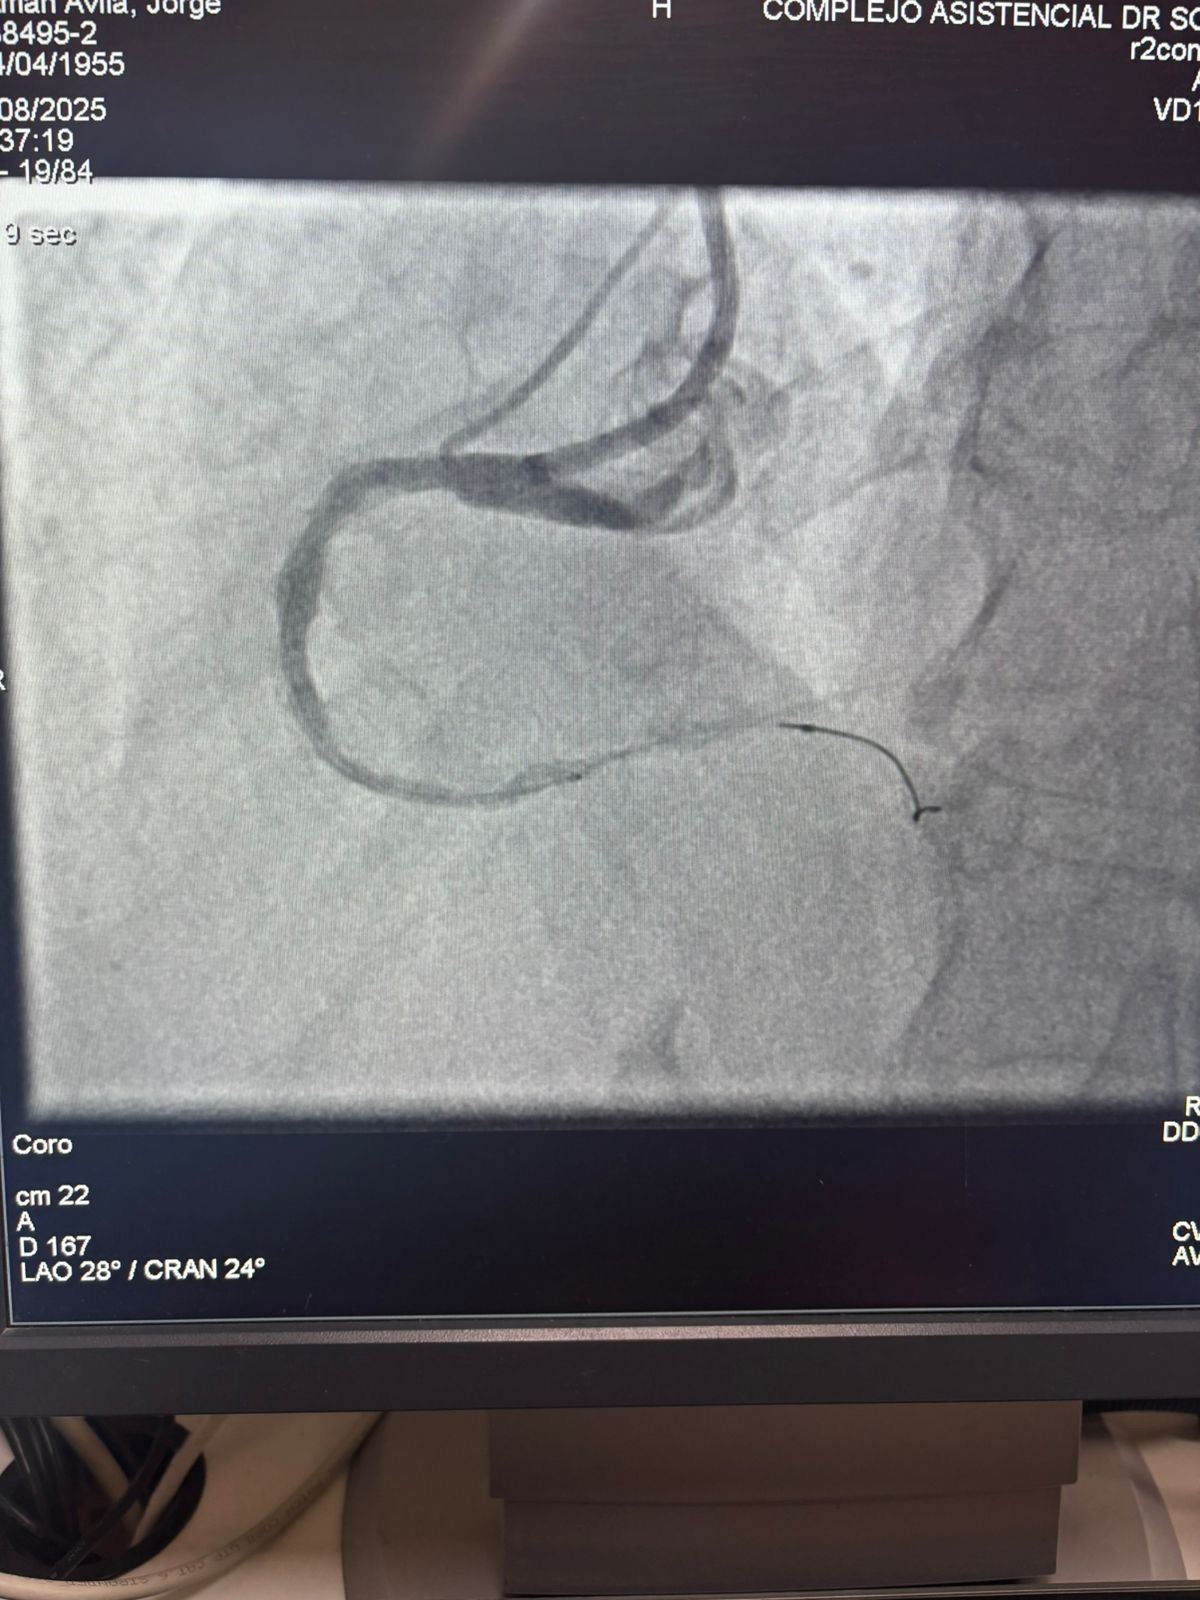

Estamos orgulhosos de compartilhar um caso notável do Hospital Sótero del Río, Chile, onde o Dr. Martín Valdebenito tratou com sucesso uma lesão fortemente calcificada na artéria coronária direita (primeira curva) usando nosso Sistema de Cateter de Dilatação Coronária Vesscrack.

O procedimento alcançou excelentes resultados, com a região calcificada efetivamente rachada e o fluxo do vaso restaurado. Isso marca outro marco na expansão do acesso global a soluções avançadas para calcificação coronariana complexa.

A comparação entre as imagens angiográficas pré-procedimento e pós-procedimento demonstra claramente o impacto clínico significativo de nossa tecnologia IVL.